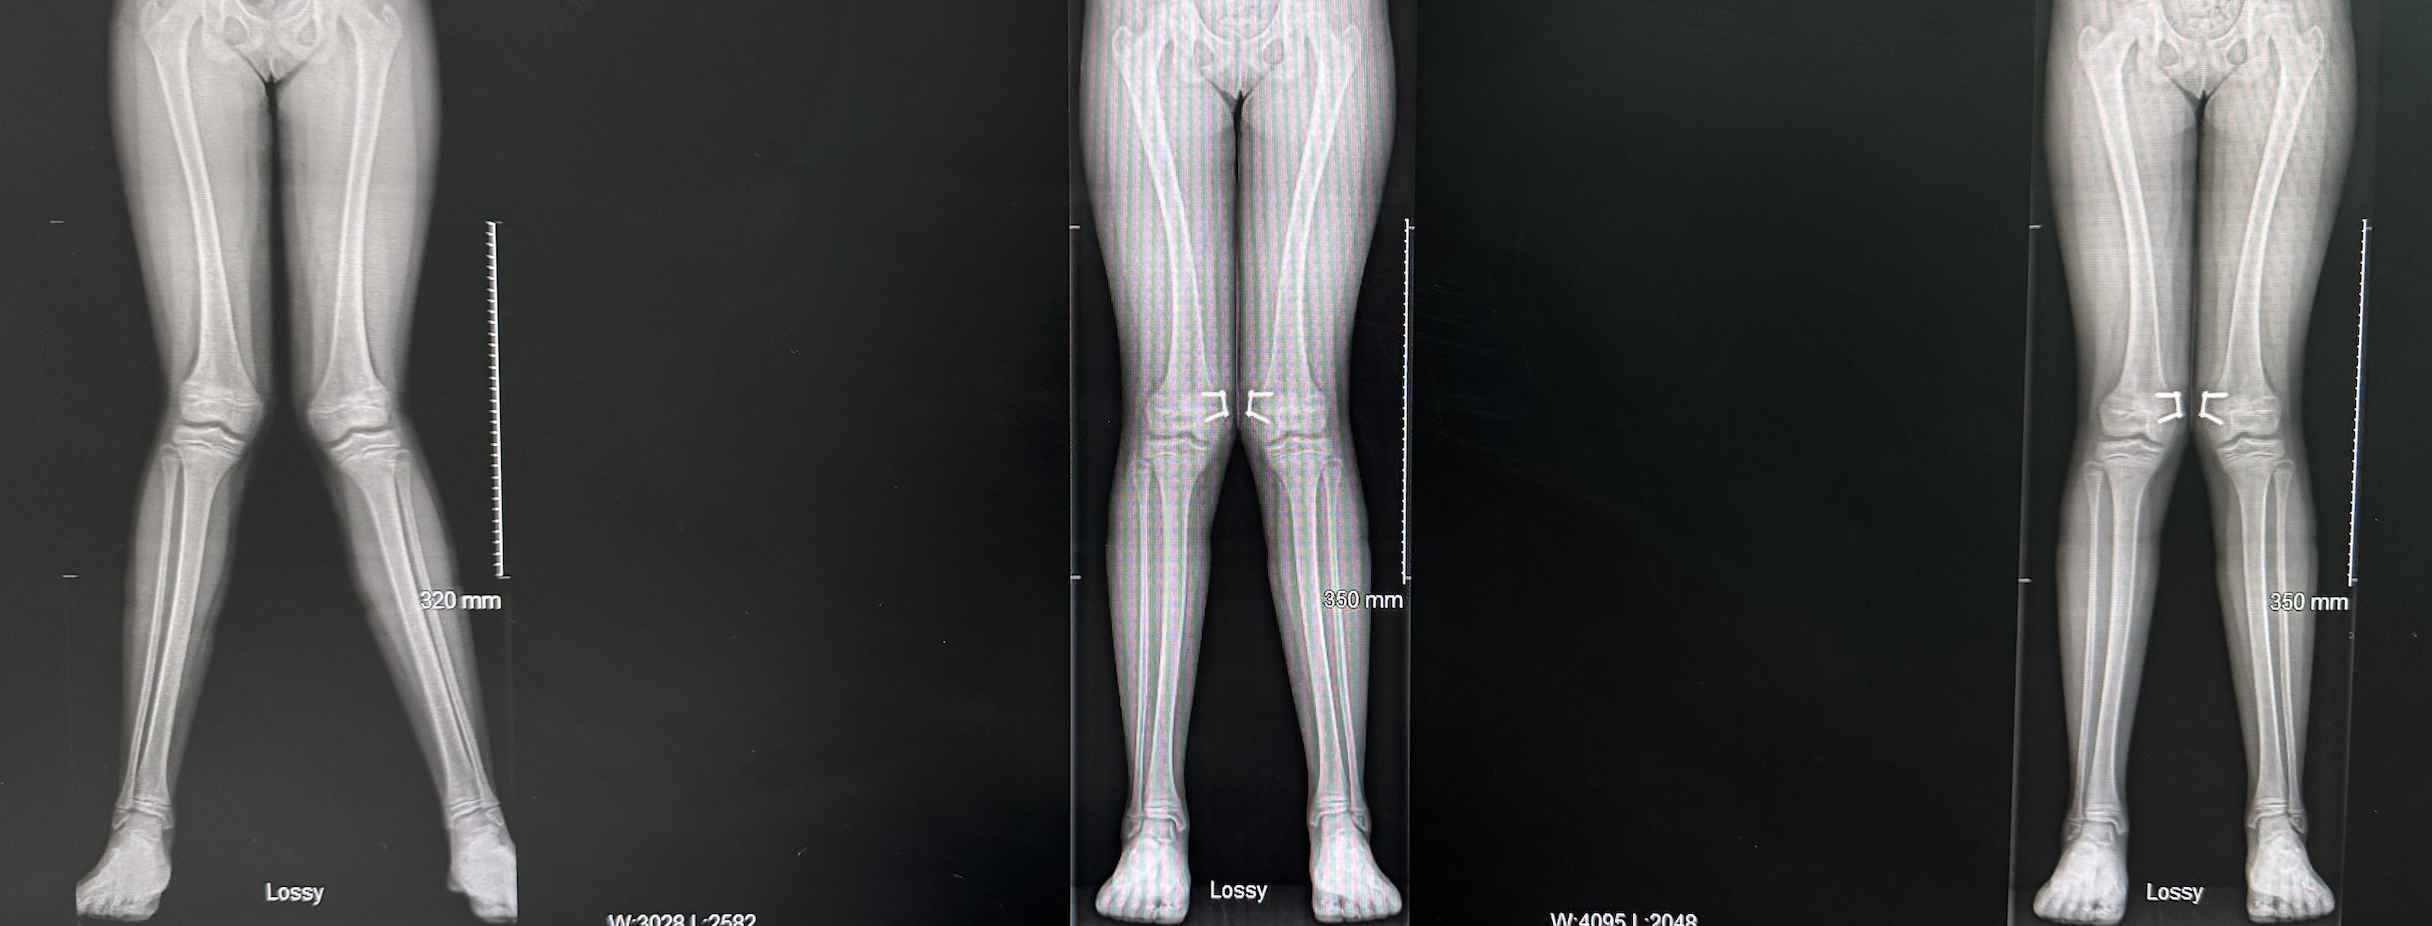

Genu valgum after femoral 8 plate correction

Same patient as above 12 months after correction with femoral 8 plates by Professor Gupte

Same patient as top of page 18 months after genu valgum correction with femoral 8 plates by Professor Gupte